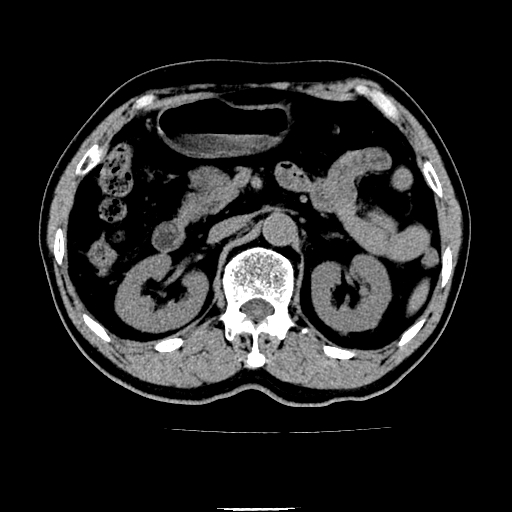

以下是引用chenqiong在2010-3-25 20:56:00的发言:[br]1、胆囊炎,胆囊息肉[br]2、肝内胆管及胆总管扩张,胆总管下端结石[br]3、十二指肠乳头旁憩室

以下是引用zxl51642在2010-3-26 10:47:00的发言:[br]胆囊炎,胆囊息肉,胆总管扩张,但未看到明显肿块,肝内胆管扩张不像恶性,炎性狭窄或阴性结石可能吧,建议mrcp,右肾小囊肿